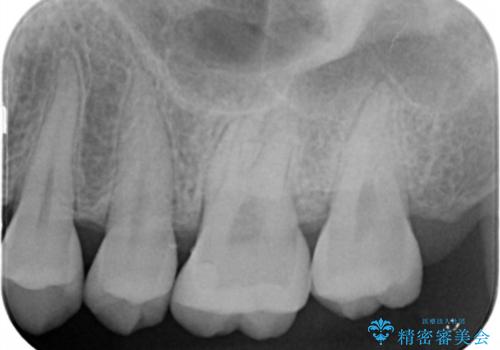

- 歯が黒くなってきているのが気になるとのことで、レントゲンを撮影し診断を行いました。

幸い神経までは到達していない虫歯だったため、部分的な詰め物「インレー」で治療を行うこととなりました。